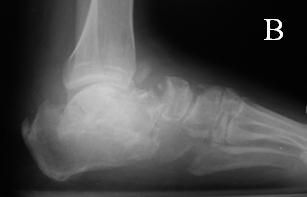

Charcot neuroarthropathy is a major cause of morbidity for patients with diabetes mellitus (DM). The foot of a 55-year-old man with a significant past medical history of type 2 DM is seen in the accompanying Figure A. He has a history of peripheral neuroarthropathy with a 1-week history of a hot, swollen right foot. A radiograph of the foot revealed acute stage Charcot neuroarthropathy (Figure B).

Figure B